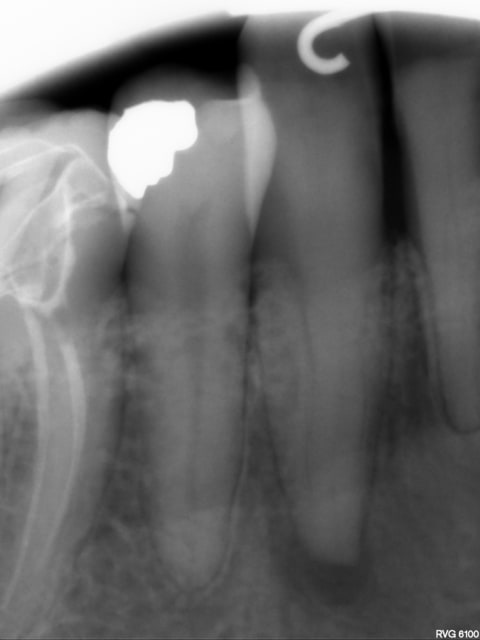

Que faire sur cette 43 nécrosée ?

sensibilité apicale à la palpation.

Mortification lié à un traitement orthodontique violent

Disparition de la lumière canalaire...

Image RVG THD6100.

Canal non ?

en tout cas on le voit. très difficilement sur la partie coronaire mais sur les autres 3/4 on le voit.

avec cette radio oui ça a l'air faisable mais racine bifide.

si la dent n'est pas bifide elle a l'air d'avoir une section en 8, et donc ptètr 2 canaux , mais avec un microscope ça doit se reperer.